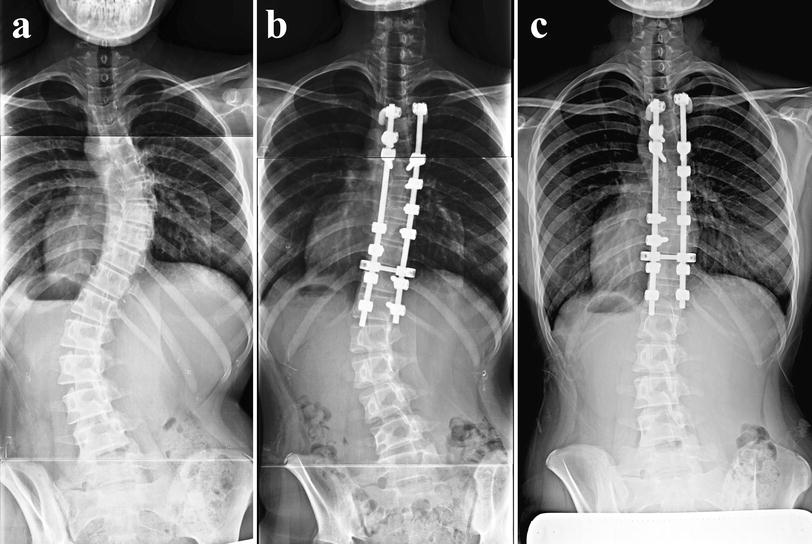

Typical cases of the classification system. Three types of coronal What Is Coronal Balance Coronal balance is another key factor in patient satisfaction. The spine and the body function within a cone of equilibrium with the focus of maintaining sagittal and coronal alignment with minimum energy expenditure. The restoration of coronal balance reduces several cosmetic deformities including having one shoulder higher than the other. Coronal plane decompensation is the most useful tool in assessment. What Is Coronal Balance.